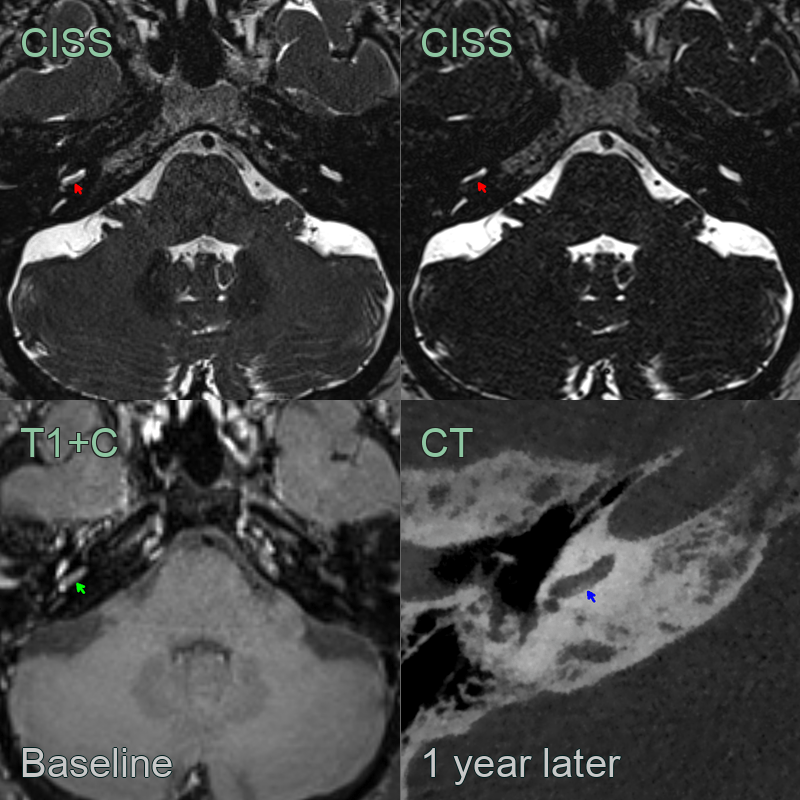

- Baseline scan showed very subtle loss of fluid signal and post-gadoliniujm enhancement in the scala tympani on the right.

- On follow-up imaging 1 year later, CSF signal had further reduced with evidence of ossification on CT.